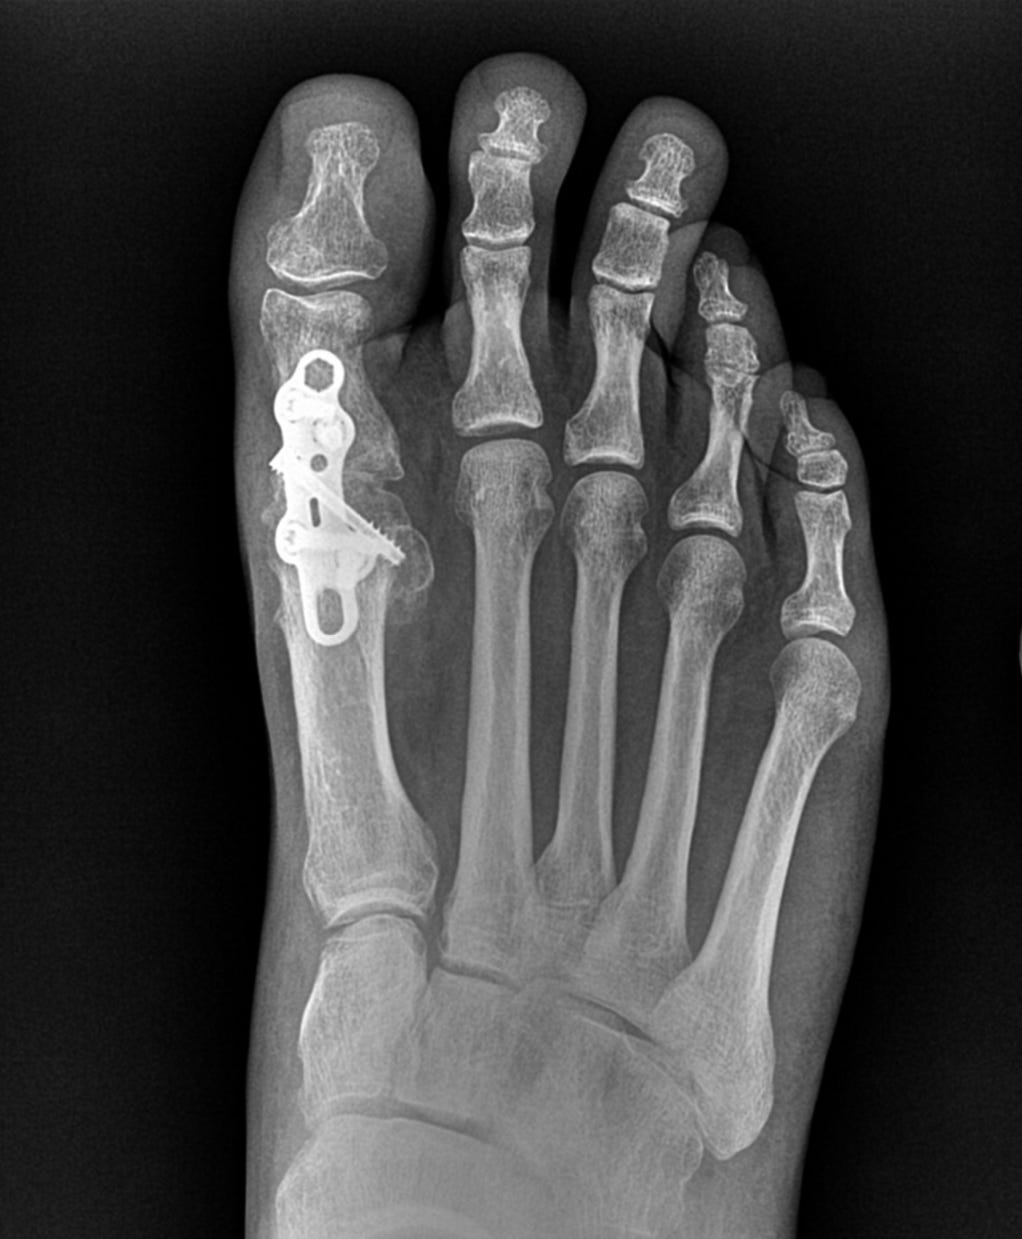

After limping around in pain for seven years, I decided it was time to have foot surgery. I couldn’t put any weight on it for six weeks after the surgery, so I had two scooters in the house to motor around on. I chose not to include the really gross post-surgical photo.